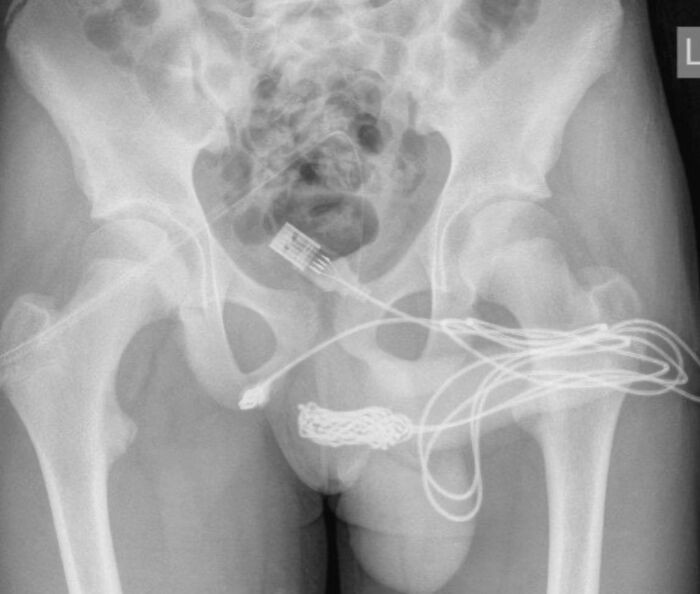

Cậu thiếu niên bị sợi dây cáp tụt sâu vào trong cơ thể.